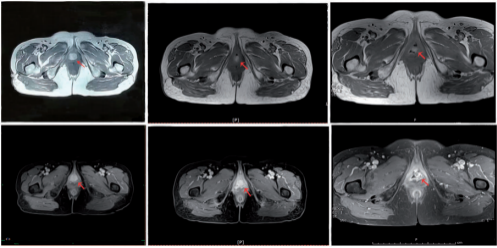

Figure 5. Comparison of imaging data before carbon ion radiotherapy, 90 days after carbon ion radiotherapy (partial response), and 180 days after carbon ion radiotherapy (partial response).

During CIRT, dysuria and frequency (up to 9–10 times/day) occurred from the seventh fraction of treatment. These symptoms were considered to have been caused by radiation-induced urethral edema, and they were relieved by symptomatic treat ment. Skin and mucosal erythema in the irradiated field occurred 10 days after the start of CIRT, as did edema of the labia major and minor, the vaginal opening, and the urethral orifice around the lesion; these were assessed as grade 1 radiation dermatitis and mucositis. The skin and mucosal adverse effects were relieved 1 month after completion of CIRT, and the dermatitis, mucositis, dysuria, and frequency of urination were totally resolved 2 months after completion of CIRT (Figure 4). No other acute or chronic adverse effects of CIRT were observed. At the end of CIRT, the tumor treatment response was stable disease. Three months after completion of CIRT, the lesion was visually smaller than before, and MRI showed that the maximum tumor diameter was about 17mm with a 32% reduction (partial remission). The lesion completely disappeared 1 year after treatment (Table 1, Figure 5, and Figure 6). The patient declined other systemic treatment after CIRT for personal reasons. As of November 2021, 33 months after CIRT, the patient was alive and disease-free. She was satisfied with the outcome of CIRT. No severe reactions were observed.